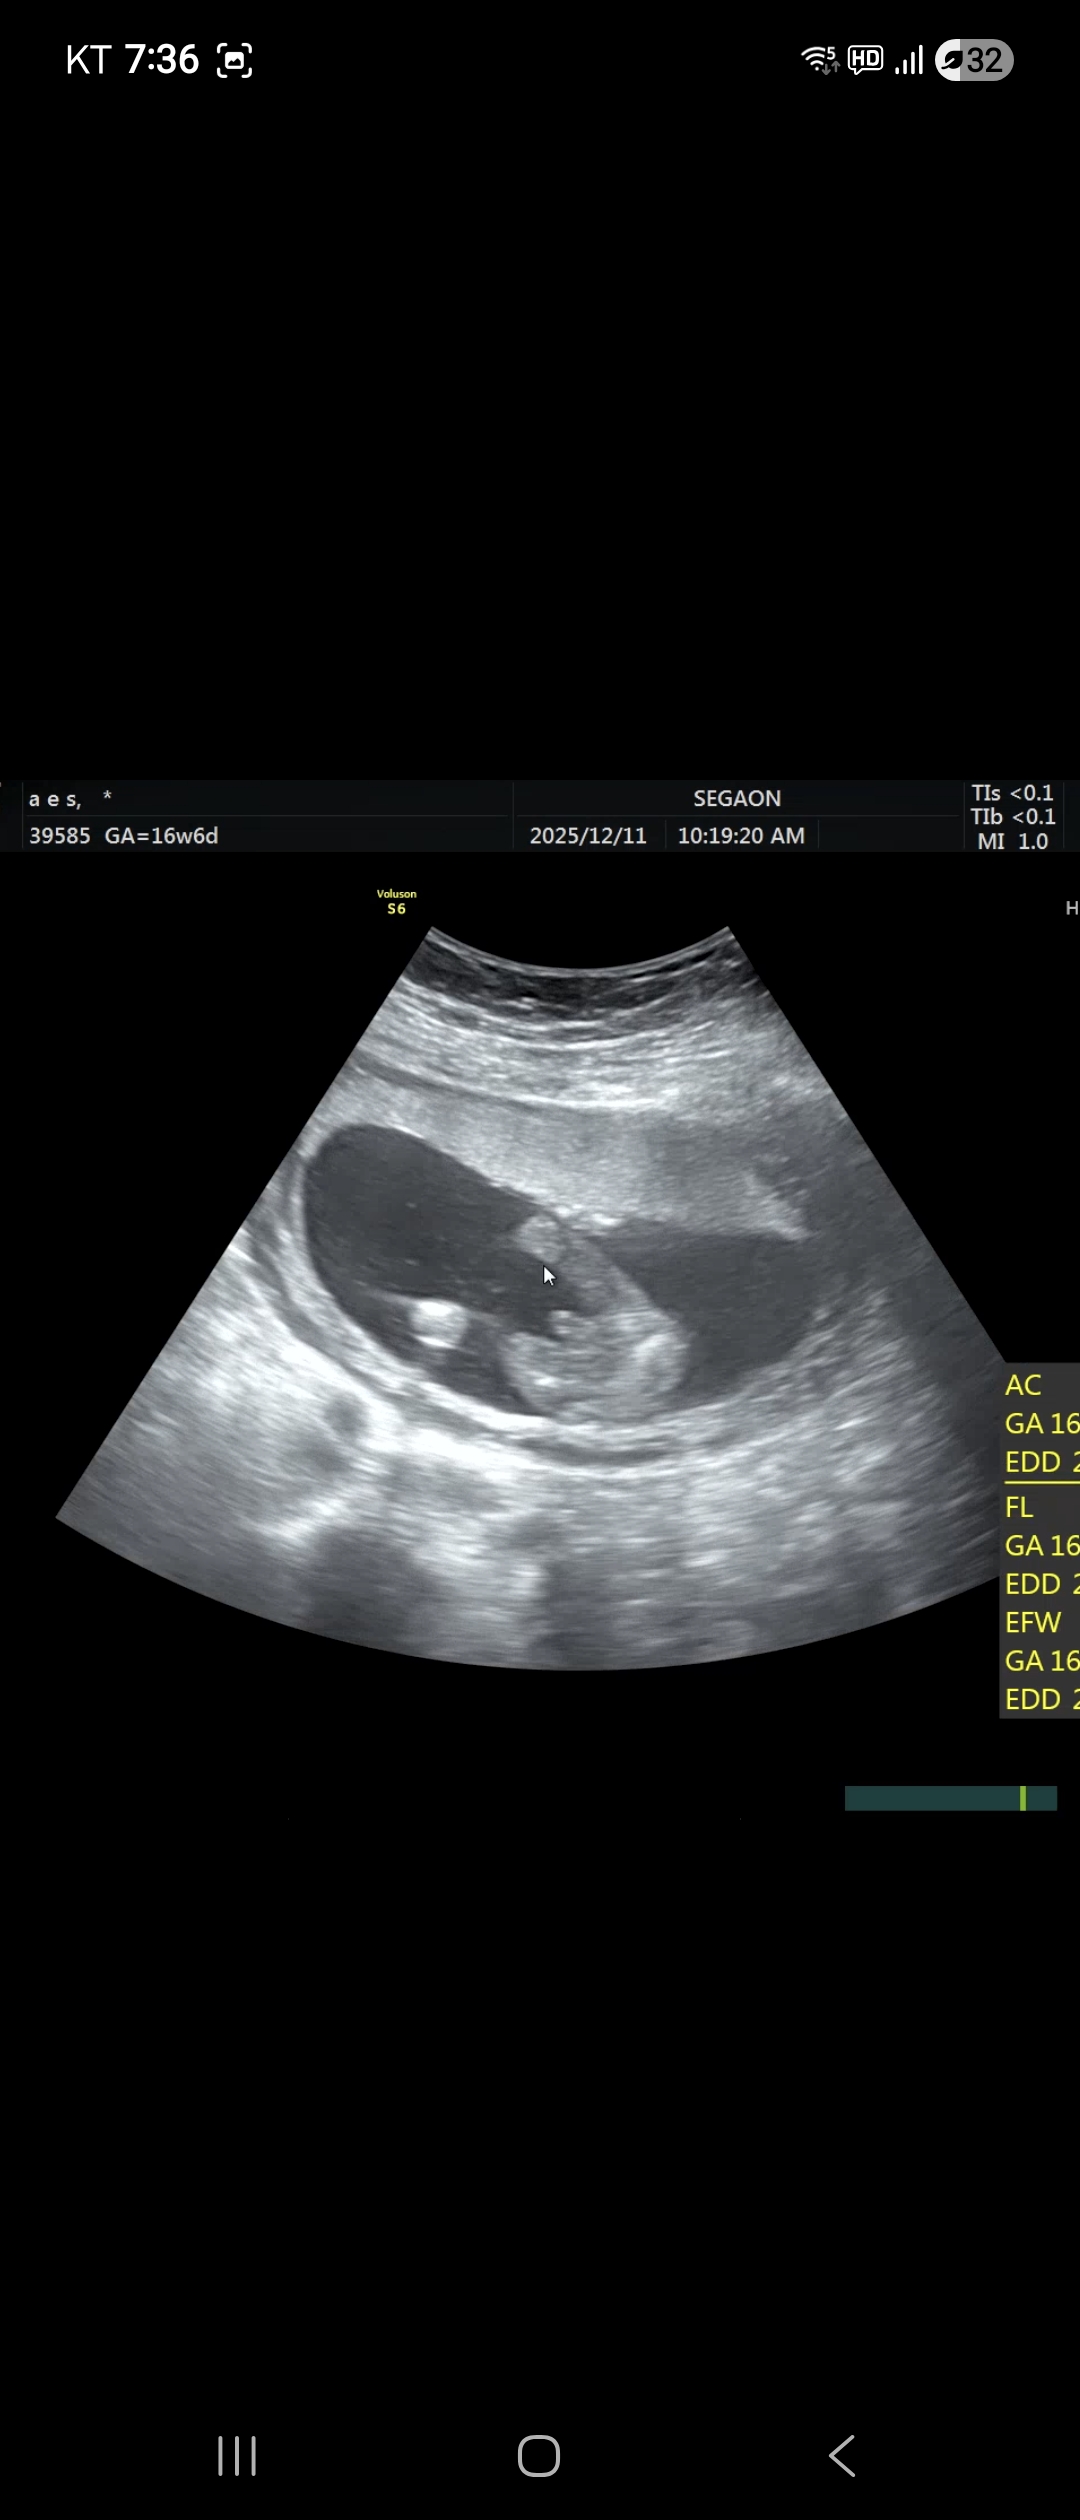

16주6일 성별확인하고 왔는데. 아들에서 딸로바꿀가능성있나요

안녕하세요 넷째임신중이다둥이엄마입니다 첫째부터섯째까지다 연년생 아들있습니다 당연히 넛째딸이라고생각햇는데 오늘성별확인결과 넷째도 아들판단 받고 말았습니다 혹시 인터넷글보고 아들에서딸되는겨우드물다지만 가능성 있다고 듣었습니다 혹시가능성보인까요

백프로아들이에요!!

아니요.. 무조건 아들이네요ㅎㅎ!

네..ㅎㅎ 16주면 반전없습니다..